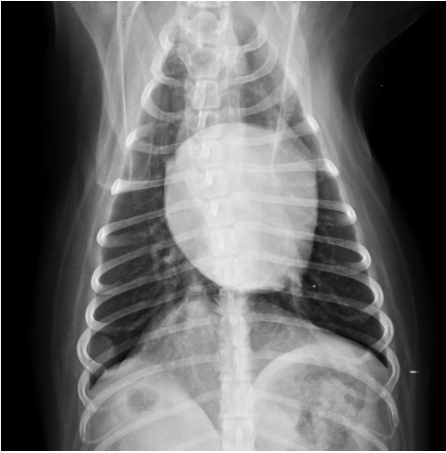

胸腔x光評估胸腔有無團塊,心臟大小;如果有心包囊積液,心臟會呈現圓且大的型態 (球形)。心臟超音波下評估心臟功能,心臟內外有無團塊樣組織,有無心包囊積液。

圖左為 患犬無心包囊積液時的心臟

圖右為 同一隻患犬心包囊積液後,